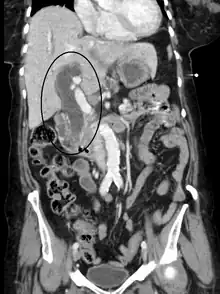

Imaging

Medical imaging such as ultrasound, CT scan, and HIDA scan are useful for detecting bile-duct blockage.[41]